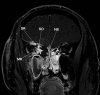

Invasive fungal sinusitis causes painful orbital apex syndrome with ophthalmoplegia and visual loss; the mechanism is unclear. We report an immunocompromised patient with invasive fungal sinusitis in whom the visual loss was due to posterior ischaemic optic neuropathy, shown on diffusion-weighted MRI, presumably from fungal invasion of small meningeal-based arteries at the orbital apex. After intensive antifungal drugs, orbital exenteration and immune reconstitution, the patient survived, but we were uncertain if the exenteration helped. We suggest that evidence of acute posterior ischaemic optic neuropathy should be a contra-indication to the need for orbital exenteration in invasive fungal sinusitis.